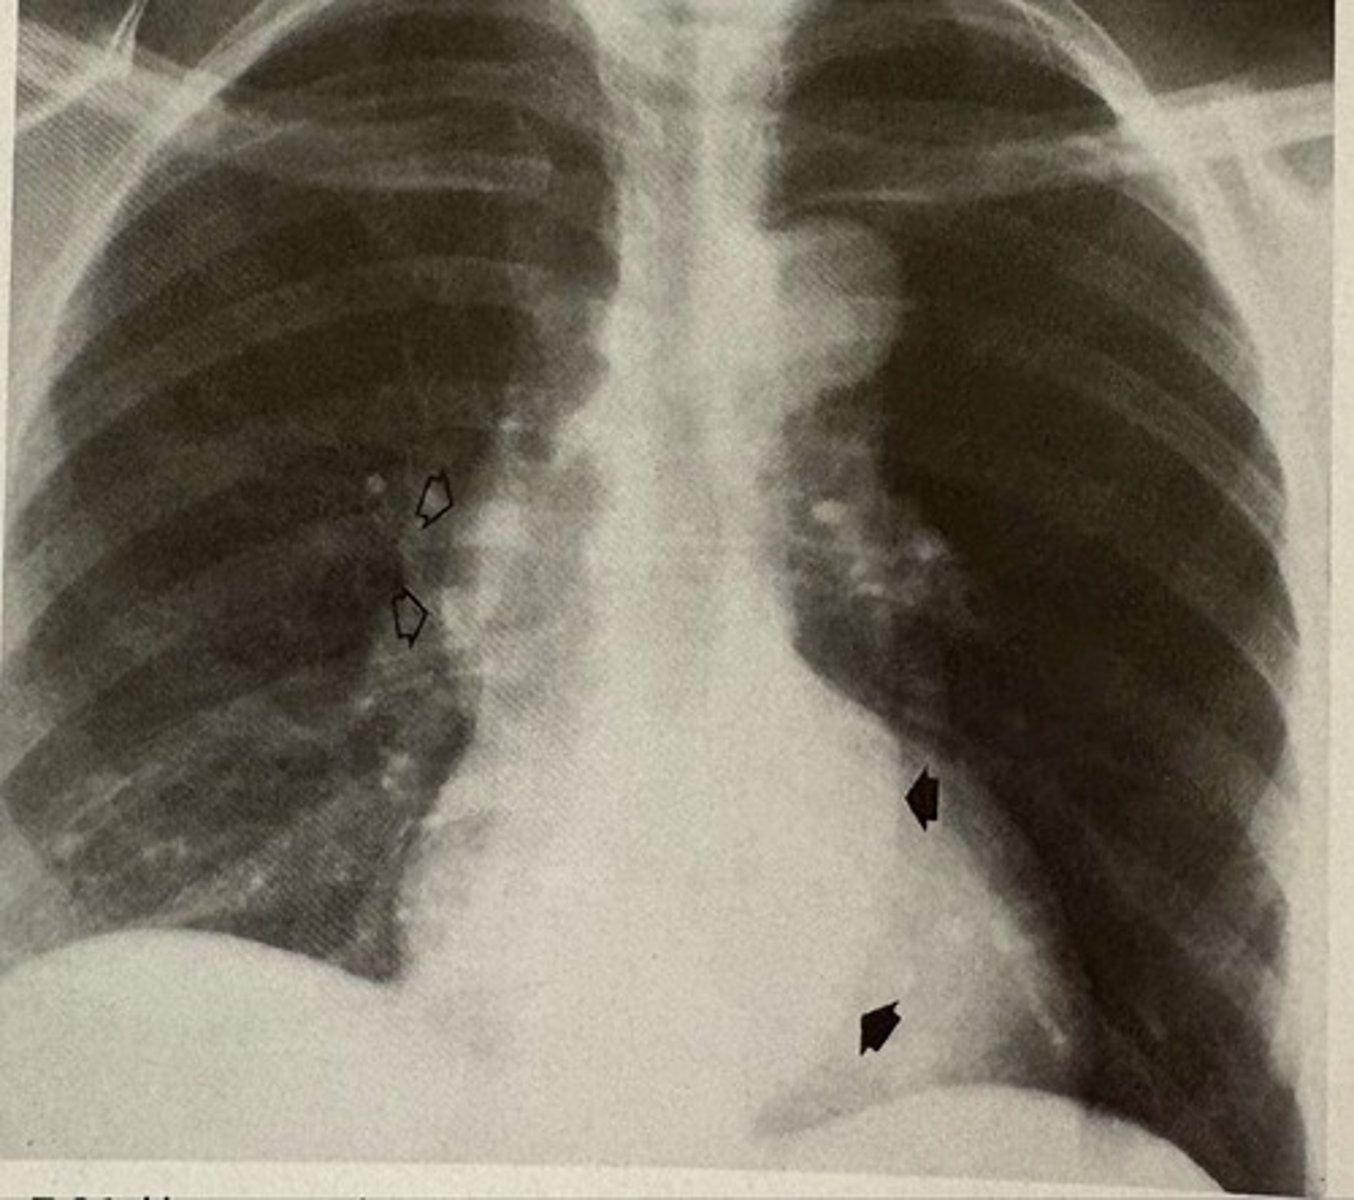

prosthetic aortic and mitral valves

what pathology is present?